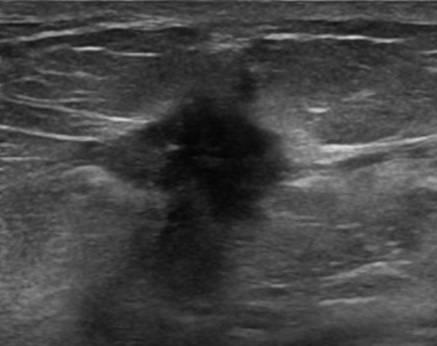

Ung thư vú

» Thông tin: Nữ giới – 55 tuổi.

» Lâm sàng: Khối tuyến vú.